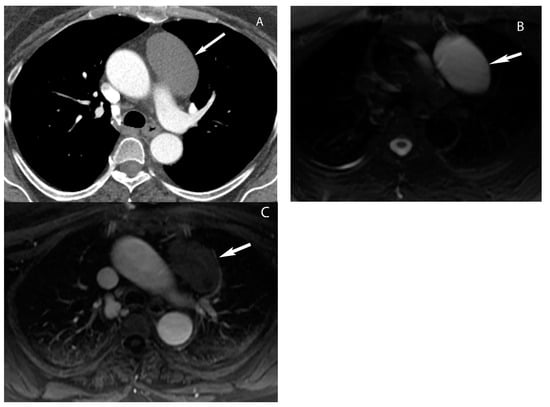

2. Imaging Modalities

Paravertebral (Posterior) Compartment